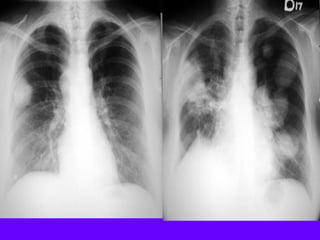

Vague density right lower lung field

Indistinct right cardiac silhouette

Intact diaphragmatic silhouette

Density corresponding to RML

No loss of lung volume

RML pneumonia